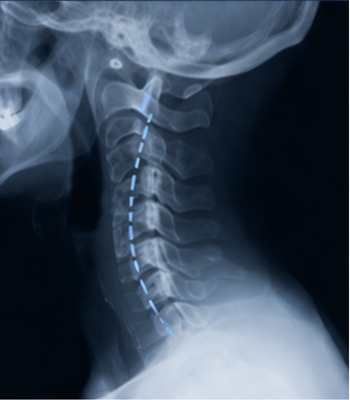

Fase 1 – Inicio

Pérdida de la curva normal. Aunque este proceso puede ocurrir en cualquier parte de la columna, es más fácil de observar en el cuello. Se puede revertir con cuidado quiropráctico.